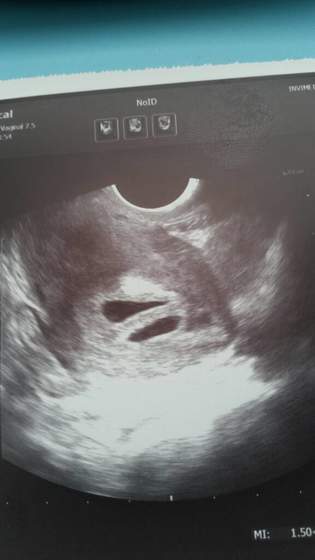

16: DorotaMie - USG i dwa cudowne serduszka